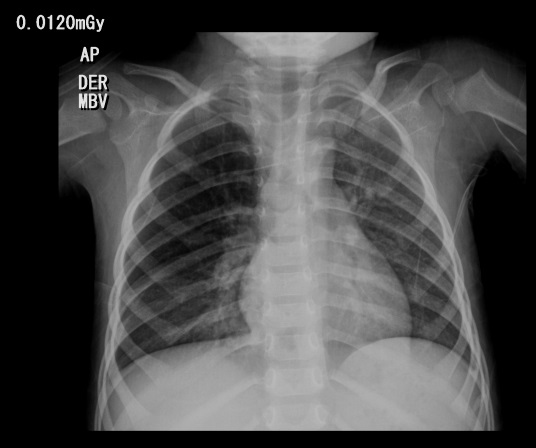

A su ingreso se administra oxígeno por cánula y se solicita radiografía de tórax reportada dentro de parámetros normales. Se considera diagnóstico de episodio sibilante y se inicia manejo con broncodilatador y oxígeno. La evolución clínica es desfavorable, con persistencia de picos febriles e incremento de trabajo respiratorio, por lo cual se realiza radiografía de tórax control 3 días después que muestra neumonía multilobar (Ver imagen 1). Adicionalmente se realizan hemocultivos y se inicia cubrimiento antimicrobiano con ampicilina sulbactam. Se inicia también tratamiento con oxígeno por cánula, salbutamol y beclometasona en inhaladores. Fue valorado por el servicio de infectología pediátrica, quienes consideraron continuar cubrimiento antimicrobiano y seguimiento de hemocultivos, los cuales finalmente resultan negativos.

Figura 1. Radiografía de tórax.

Infiltrados mixtos predominantemente alveolares bibasales por neumonía multilobar sin evidencia de derrame pleural.